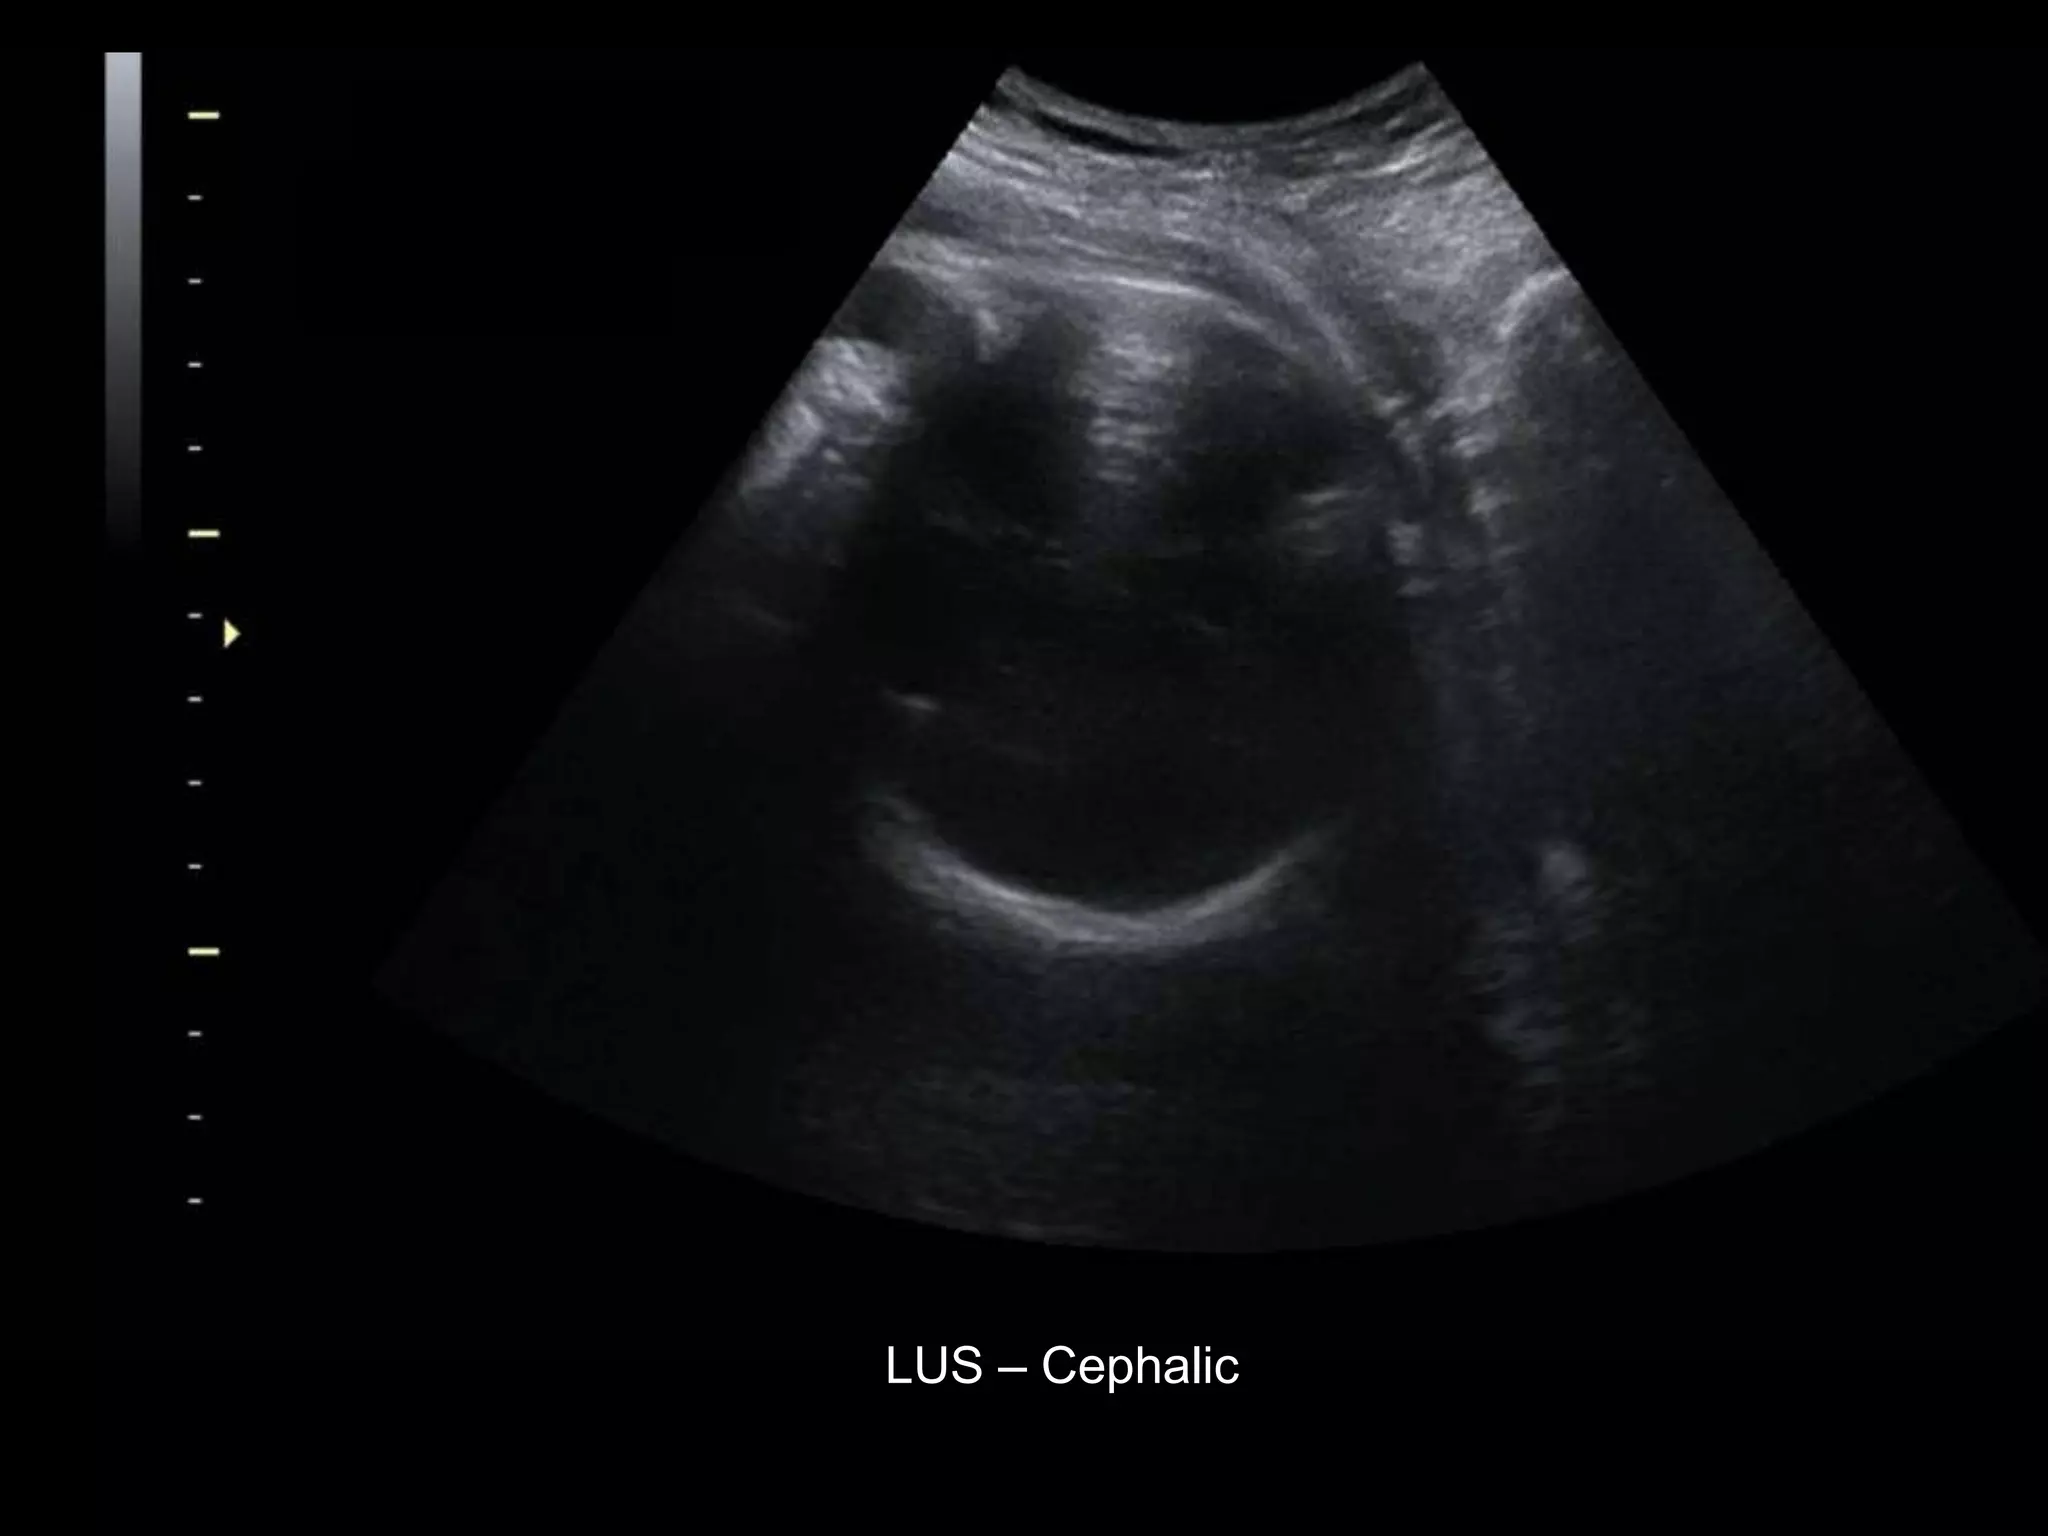

HISTORY

โ€ข 36 yo female 30.5 weeks pregnant

โ€ข Referred with โ€žmultiple fetal anomaliesโ€Ÿ for

fetal ultrasound

LUS โ€“ Cephalic